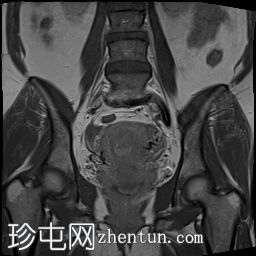

轴位

STIR序列

可见子宫外腹腔内妊娠囊,内含胎儿组织。

该妊娠囊向后推移子宫,并与剖宫产瘢痕凹陷处紧密相连。

该妊娠囊与相关肠袢无法分离。可见其与性腺血管密不可分,且性腺血管明显突出。

胎盘位于妊娠囊后方,紧贴子宫前壁。

沿妊娠囊下缘可见一处异质性局灶性积液,最大轴向尺寸约为 8.4 × 5.5 cm,T1 加权像呈异质性高信号,T2 加权像呈异质性中等信号,T1 脂肪抑制序列未见信号下降,提示为血液成分。该积液压迫膀胱。

可见周围脂肪间隙呈条索状改变。

左侧卵巢无法辨认。

右侧卵巢未见实性或囊性肿块。

子宫体积增大,后倾,子宫内膜厚度约 1 cm,子宫下段前壁可见局灶性变薄(既往子宫瘢痕)。子宫连接区完整,未见肌层肿块。可见子宫内膜腔边缘有血性分泌物。